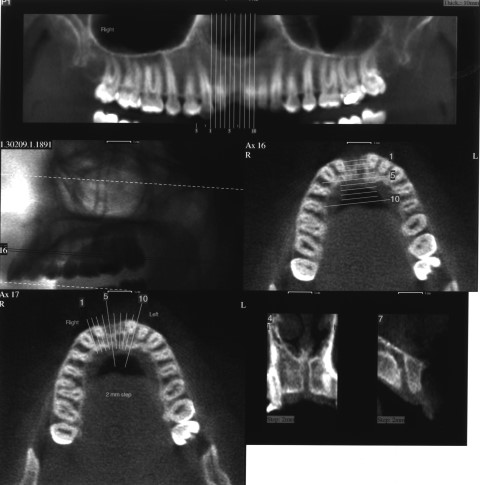

לאחר 3 חודשים מיום העקירה ביצוע צילום סיטי (טומוגרפיה ממוחשבת) לצורך תכנון ביצוע שתל בודד עם עיבוי העצם